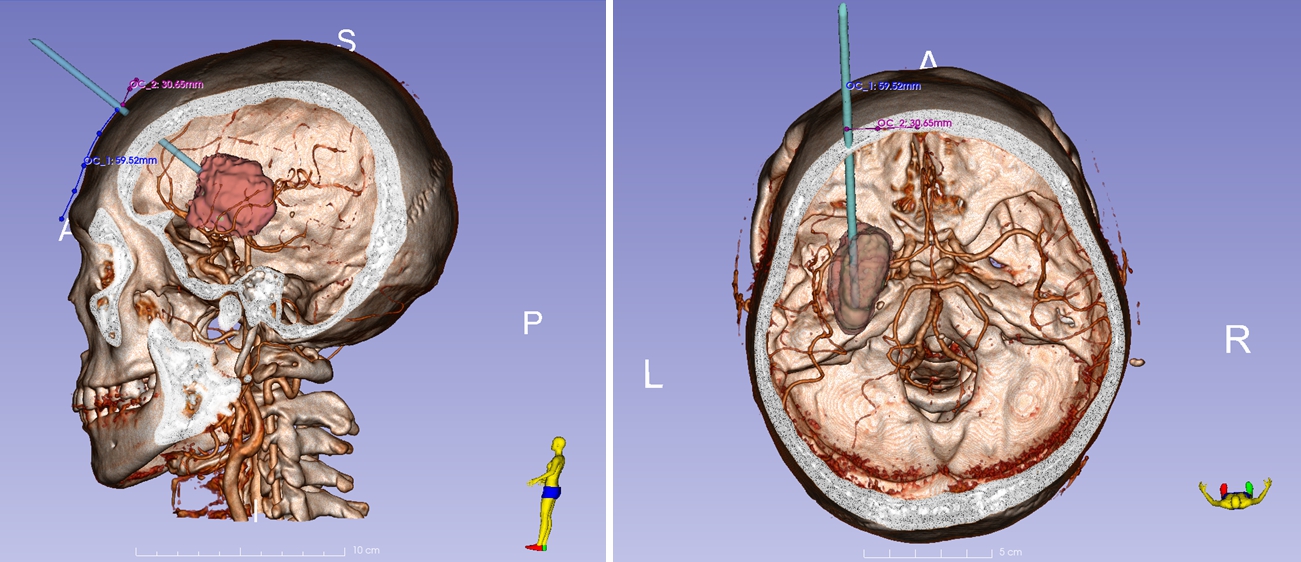

入院后,完善脑血管CTA,排除动脉瘤及血管畸形等疾病。经三维重建可见血肿有分层,血肿体积27.83ml,设计经额穿刺通道,发际内,中线旁开3.0cm,有效避开动静脉血管,利用激光定位系统,靶向精准穿刺置管引流,术后复查引流管位置满意,患者肢体功能明显好转,恢复良好。

数字化定位穿刺部位

发际内,中线旁开3.0cm

有效避开额部血管